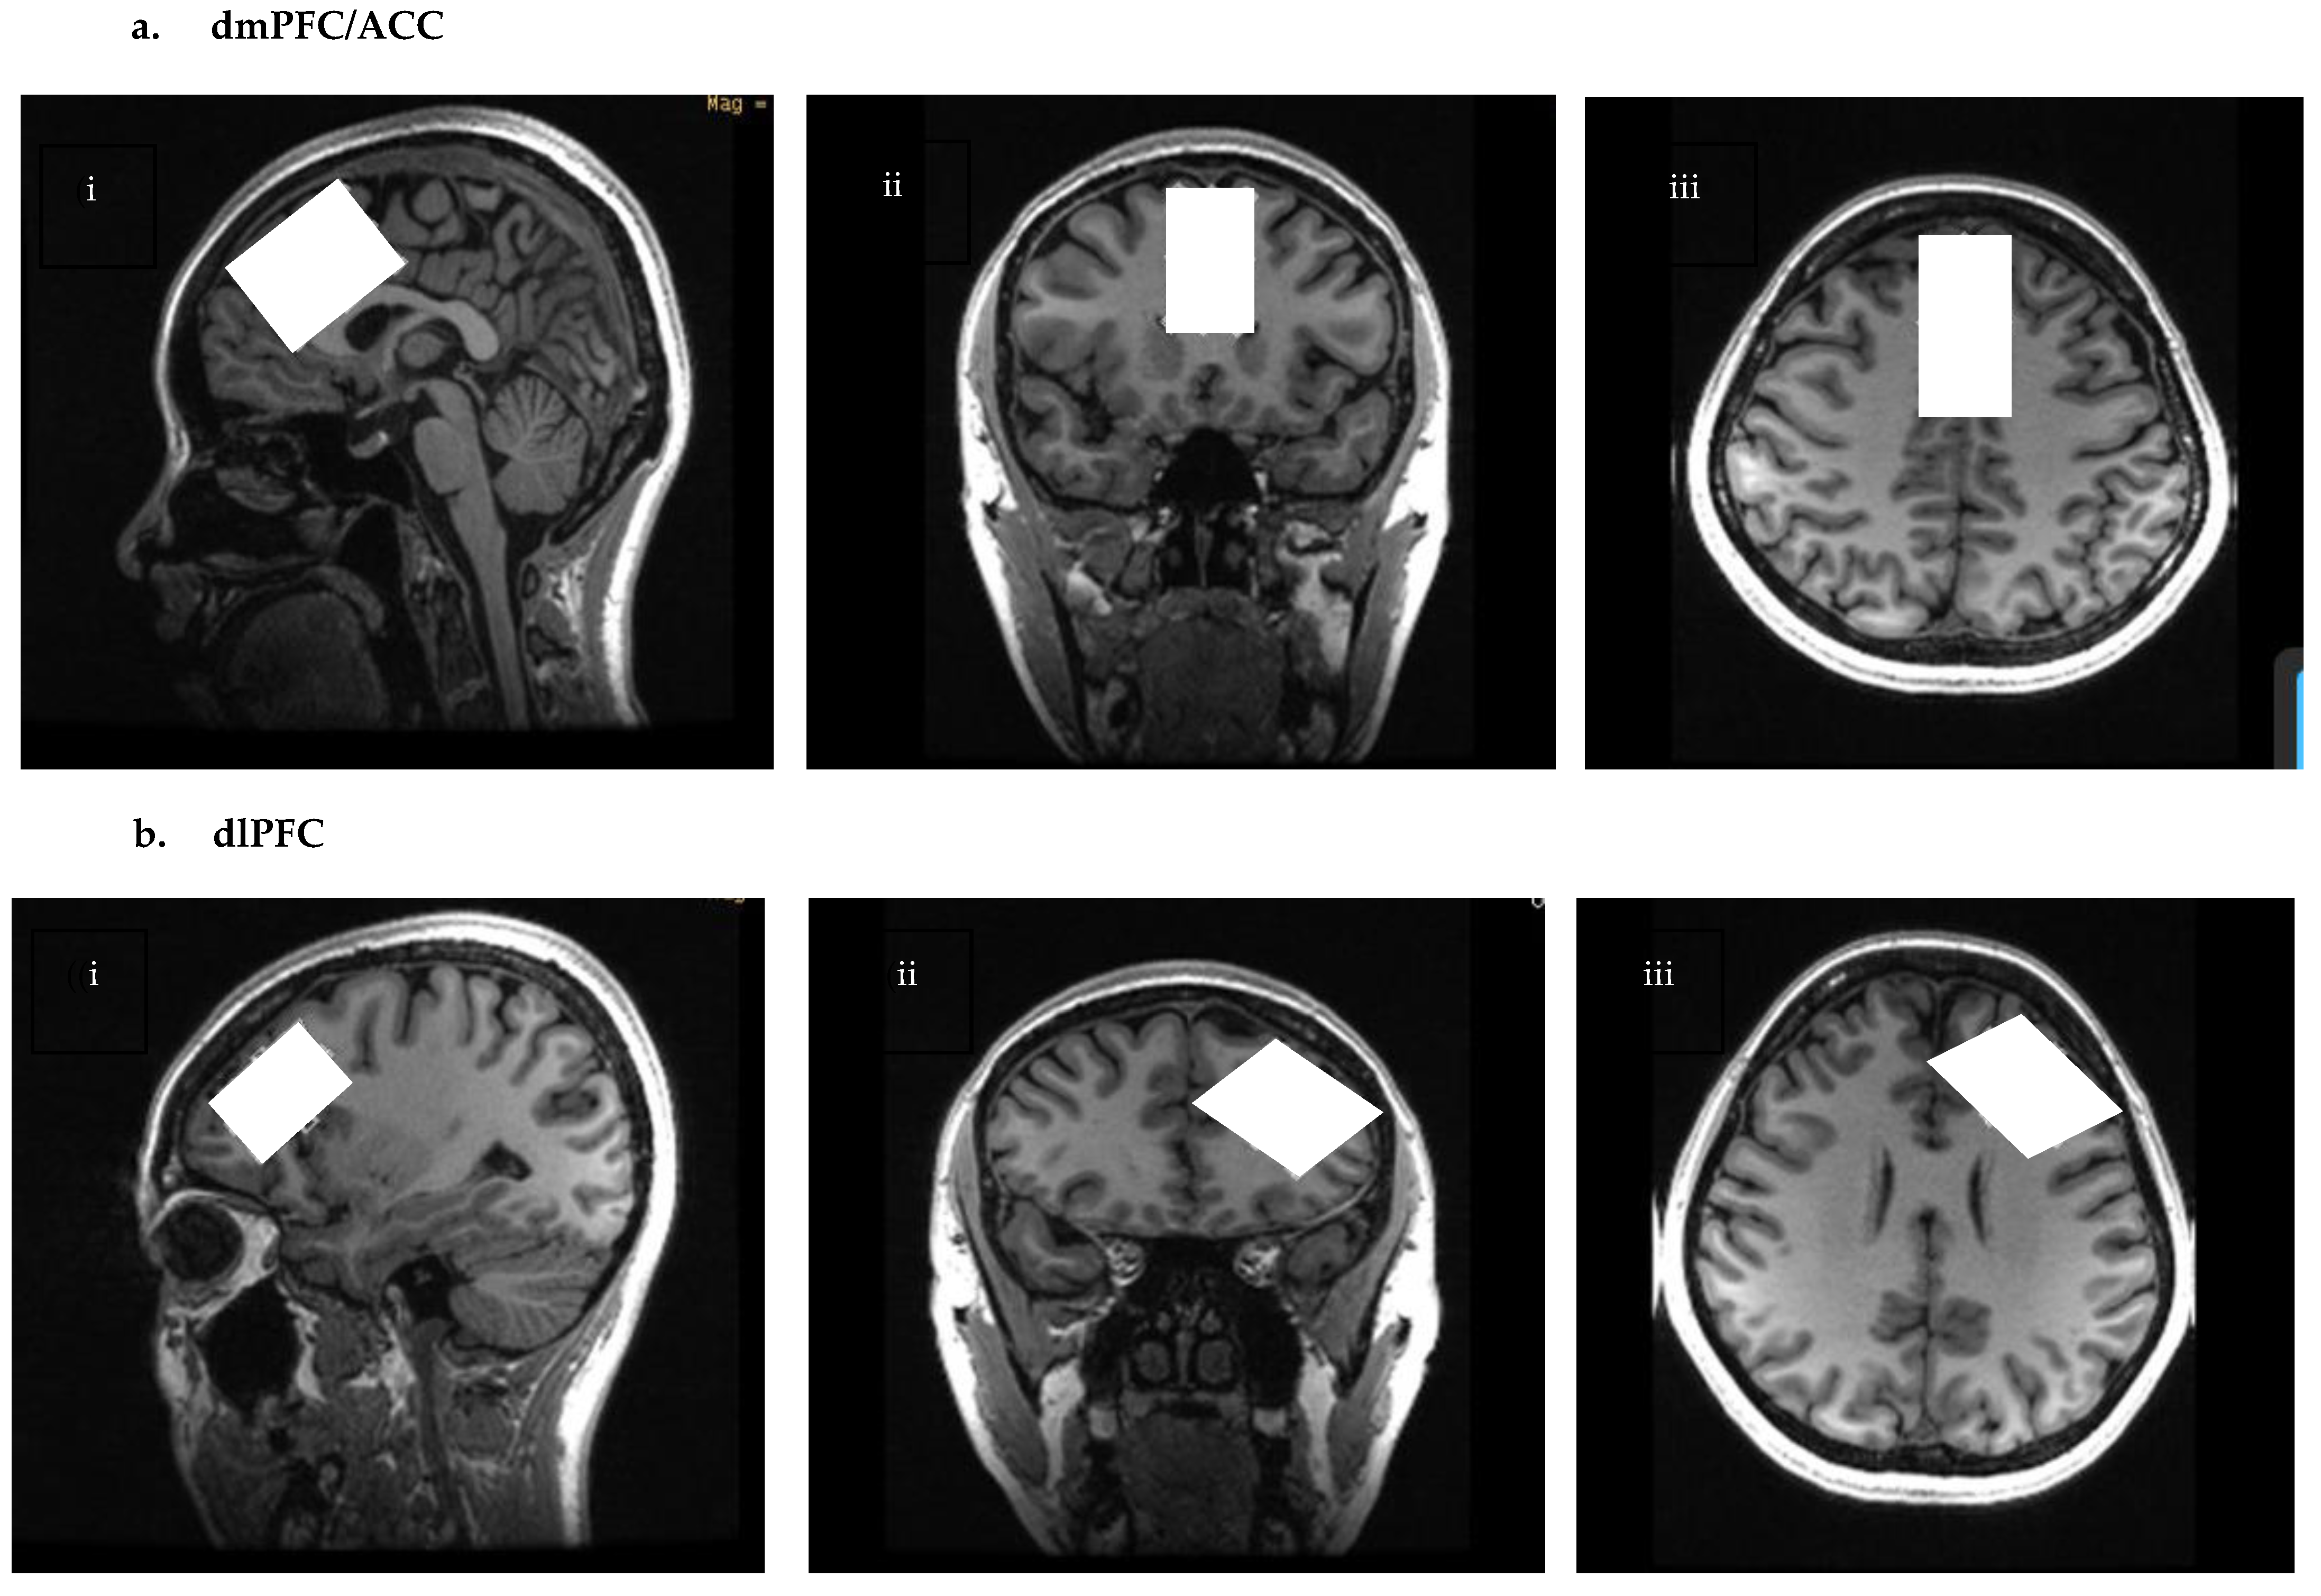

2.1.1. dmPFC/ACC

2.1.2. dlPFC